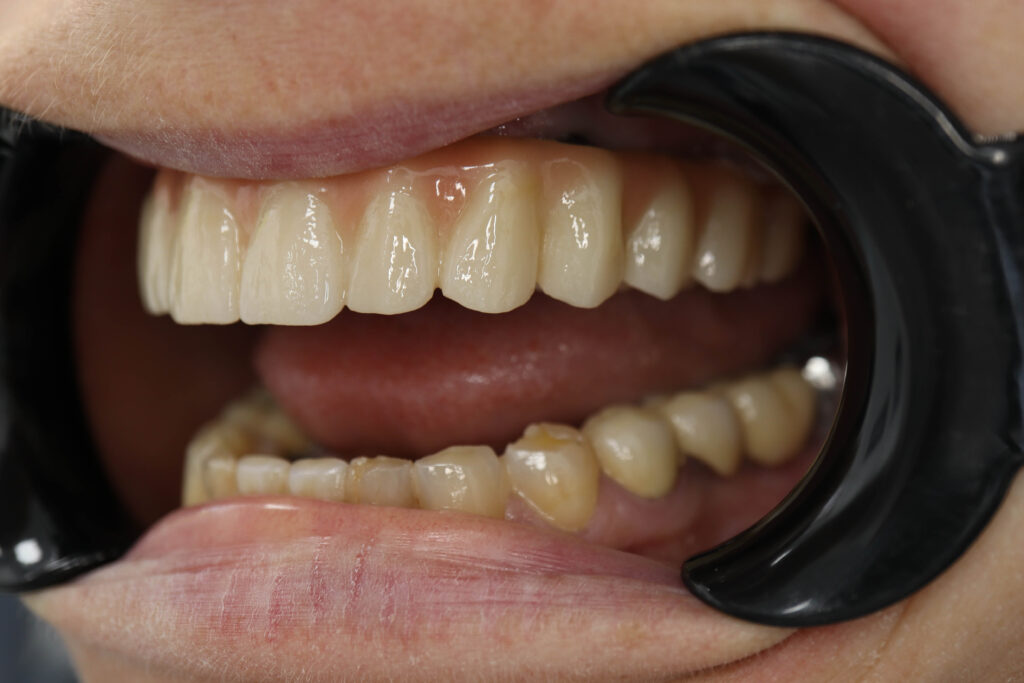

Спустя 25 дней был зафиксирован протез с опопрой на дентальные имплантаты из диоксида циркония.

Результаты

снимок